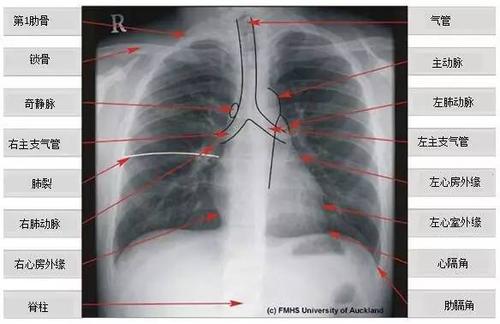

超详细胸片教学 不信你还学不会!

"0"基础小白必备宝典:认识肺部影像结构

正常胸片图片图解

肺部正常胸片影像图片

正常胸片影像图片